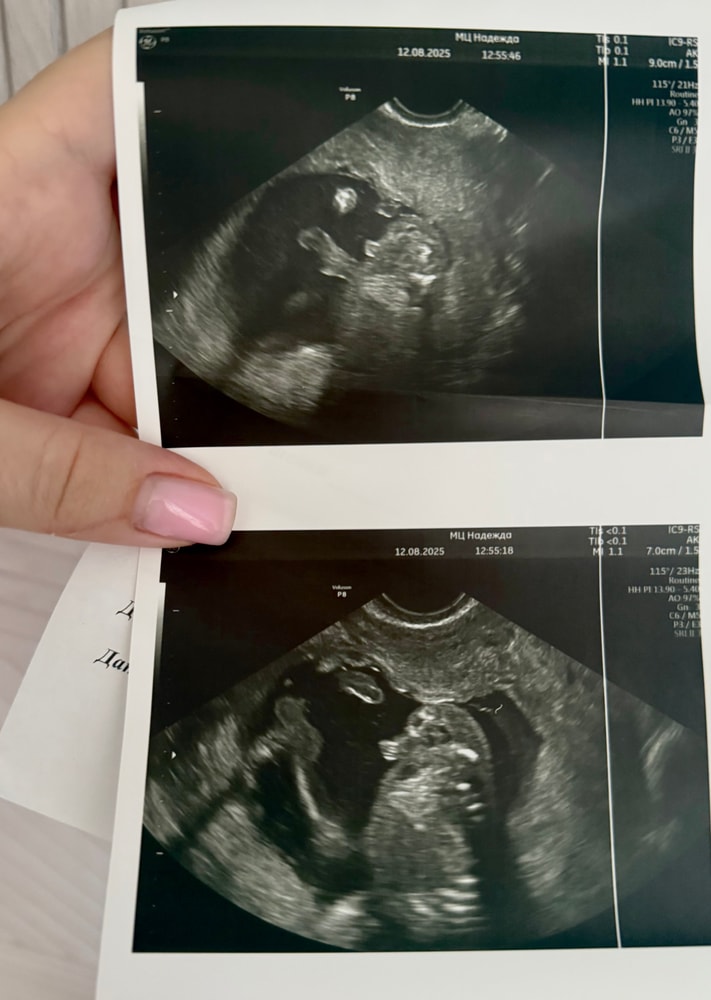

Пол малышаВсем привет🌸Вчера писала пост по поводу узнавать пол или нет.Сегодня с утра сходила на цервикометрию.Процедура длилась одну минуту,врач просто померил шейку и послушал сердцебиение.Даже не успела спросить может ли он пол посмотреть,вот так все быстро было.Пока шла домой не могла прям успокоится,позвонила в одну клинику,там сегодня все занято,а во второй сказали через 20 минут приходите.Как раз я была недалеко,прогулялась.Врач сначала удивилась мол рановато еще пол смотреть,но я все же настояла.По животу мы мало что увидели,малыш лежит ногами вниз как раз.А вагинально увидели сразу и очень хорошо,он нам все показал😂Еще так символично,клиника находится рядом с церквью,и мне называют пол и начинают в этот момент бить колокола.Лежала с глупой улыбкой😄Побежала скорее домой обрадовать мужа.Он знал,что я сегодня иду на узи и хочу спросить про пол.В итоге позвонил и спрашивает сказали или нет,я еле удержалась и говорю ничего не сказали(на цервикометрии же и вправду ничего не сказали).По дороге зашла в «Детский мир»,думала взять голубой бодик,но смотрю голубых там не было вообще,либо для девочек либо для мальчиков,но не голубые.В итоге взяла пустышку🍼Домой прихожу,протягиваю мужу.Он сидит в непонятках,зачем так рано соску купила.Потом понял наконец-то,когда сказала на цвет внимание обратить))Он просто воссиял,эффект неожиданности произошел.Сначала меня крутил и целовал в живот,а потом ходил с такой же глупой улыбкой как у меня по дому,мусорный пакет как раз собирал перед выходом и ходил с ним улыбался 😂Это надо было видеть.У НАС БУДЕТ СЫН!!!🩵🩵🩵Все как мы мечтали,именно о сыночке.Попросила врача еще сделать фото-доказательства,чтобы было на память.